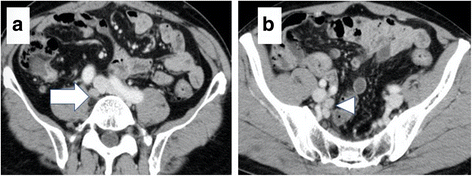

Six months after the operation, however, the patient’s serum CEA levels increased to 7.0 ng/mL. Abdominal CT revealed swollen lymph nodes in the right common and internal iliac artery area (Fig. 3a, b). Positron emission tomography (PET) with CT revealed hot spots (SUVmax, 5.3) in the same lesions (Fig. 4a, b). No other metastases were observed. Accordingly, we retrospectively re-evaluated the preoperative CT images. Although we detected no apparent swollen lymph nodes, we observed an unusual soft tissue area around the right internal iliac artery (Fig. 5). The preoperative diagnosis was an LLN metastasis localized in the right pelvic area, and an open unilateral LLN dissection of the right common iliac, internal iliac, and obturator nodes was performed. The branches of the right internal iliac vessels, including the superior vesical and obturator vessels, were ligated and divided at their origins with resected lymph nodes; however, the internal iliac artery and pelvic nerve plexus were preserved. Histologically, 15 lymph nodes were resected; of these, 3 (2 in the proximal internal iliac node and 1 in the common iliac node) contained metastases of adenocarcinoma (Fig. 2d). The postoperative course was uneventful. The patient was given 12 cycles of adjuvant chemotherapy with FOLFOX (fluorouracil, leucovorin, and oxaliplatin). He remains healthy without signs of recurrence at 30 months after the second surgery.